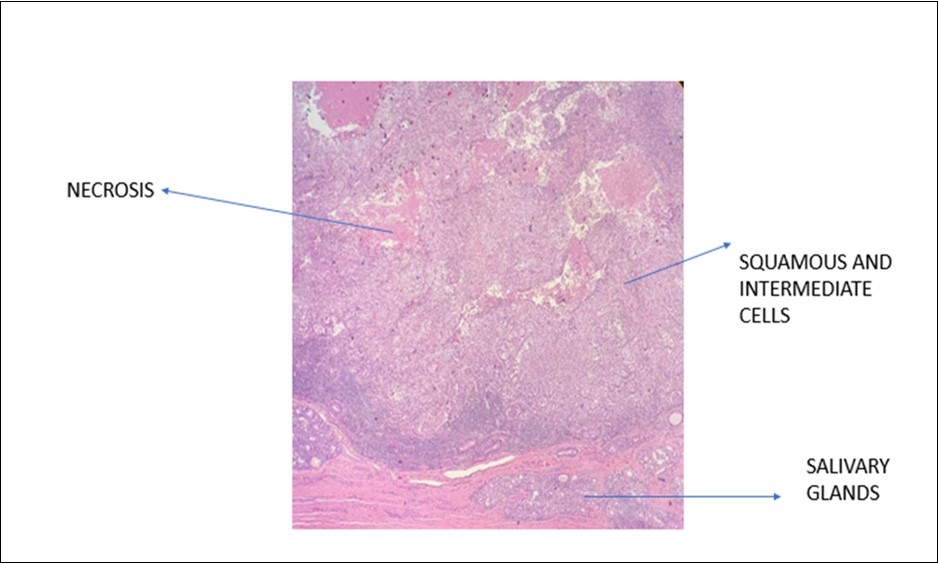

A 70-year-old gentleman, ex-smoker with no comorbid presented to us with hoarseness for 2 months in duration. He also had occasional shortness of breath. There was no constitutional symptom present. Upon our examination, the patient had soft stridor with hoarseness. There were no palpable neck nodes and laryngeal crepitus was present. On flexible nasopharyngolaryngoscopy, a fungating mass was seen occupying the whole length of the left vocal cord, with the cord in a fixed position. The right vocal cord was mobile. A high tracheostomy was done with direct laryngoscopy showing a supraglottic mass obstructing the laryngeal inlet, which is more confined to the left vocal cord and with extension into the subglottic region. Histopathology reported the mass as in favor of MEC. In microscopy, intraluminal and occasional intracytoplasmic PAS-positive diastase-resistant mucin were demonstrated. [Figure 1 & Figure 2] A contrasted-CT scan showed a huge laryngopharyngeal mass extending from the supraglottic to the infraglottic region, with no significant lymphadenopathy nor distant metastasis. The mass had no clear plane with the left thyroid and arytenoid cartilages. Subsequently, the patient underwent a total laryngectomy, left hemithyroidectomy and bilateral selective neck dissection with the histopathology reporting of high-grade MEC, with the involvement of the right level II neck node. Clinically, this is a T4aN0M0 transglottic tumor. Currently, the patient has completed adjuvant radiotherapy with monthly follow-ups at our center. He had remained well at six months follow-up.

Figure 1.Photomicrograph show presence of squamous and intermediate cells in MEC of larynx (x20 high power field)

The highest incidence of MEC in larynx mostly occurs in the supraglottic region (61%), where laryngeal glands are mostly located at. This is as shown in this case reported. The site of occurrence differs from SCC as SCC of larynx usually affects the glottis region. Laryngeal MEC has a wide range of diseases from localized invasion to highly malignant lesions as described in this article. The origin of these lesions is usually from the reserve cells in the excretory ducts of submucosal glands. It can also be from the squamous cells in the laryngeal surface epithelium. 1 Microscopically, MEC consists of 3 cell types, which are epidermoid, mucus-secreting and intermediate cells, which are histopathologically similar to any MEC lesions occurring elsewhere. Thus, recognizing these features is of utmost importance in establishing the diagnosis of these rare neoplasms. 7

On the other hand, MEC and SCC lesions are quite similar histologically, which can be tricky to establish the correct diagnosis. The presence of the intermediate and mucous cells in MEC tumors is one of the distinguishing features. 8 Performing a mucicarmine stain is also significant in identifying MEC lesions. Besides, immunohistochemistry expression of MUC-type mucin and expression of cytokeratin marker, CK 14 help establish the diagnosis of MEC. 1 As such, intraluminal and occasional intracytoplasmic PAS-positive diastase-resistant mucin were identified in the case discussed, leading to its diagnosis of MEC of the larynx.